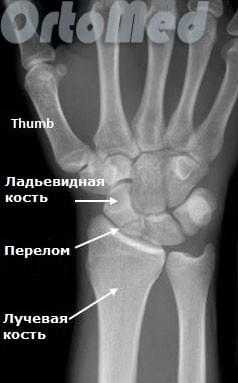

Переломы ладьевидной кости

Любая травма области лучезапястного сустава должна быть оценена врачом травматологом, так как переломы мелких костей могут быть ошибочно расценены пациентом как ушиб. Но последствия перелома ладьевидной кости руки могут быть очень серьезными (см. пояснение в тексте).

Ладьевидная кость является одной из мелких костей запястья. Из всех костей в запястья, переломы ладьевидной кости являются наиболее распространенными. Ладьевидная кость - небольшая кость запястья на стороне большого пальца (с лучевой стороны).

Ладьевидная кость имеет плохое кровоснабжение. Проксимальный полюс (ближе к предплечью) при переломах остается без кровоснабжения. Ввиду этого очень важна ранняя диагностика подобных переломов кисти.

Диагностика переломов ладьевидной кости

Очень важно диагностировать перелом ладьевидной кости как можно раньше, поскольку значительная часть ладьевидной кости имеет плохое кровоснабжение и перелом может не срастись, или наступить некроз фрагмента кости (некровоснабжаемый фрагмент погибает), а это ведет к серьезным отрицательным последствиям (ограничение движений в лучезапястном суставе).

Первым и обязательным диагностическим моментом является рентгенография поврежденного участка конечности. Чаще всего рентгенография ясно показывает характер перелома ладьевидной кости.

В некоторых случаях, когда по рентгенограмме тяжело определить соотношение отломков назначается компьютерная томография лучезапястного сустава. При таком исследовании можно трехмерно увидеть поврежденную кость, что поможет в определении тактики оперативного лечения перелома.

Если перелом ладьевидной кости происходит без смещения отломков, то линию перелома на рентгенограмме можно и не увидеть. Поэтому очень важно при любой травме кисти выполнить шинирование на 10 дней. На 10 день повторить рентгенограммы кисти и, если перелом все же был, он станет четко просматриваться. Ну а далее выполняют соответствующие лечебные мероприятия (см. раздел лечение переломов ладьевидной кости).

Асептический некроз: Часть ладьевидной кости может некротизироваться (отмирает) из-за отсутствия кровоснабжения, что приводит к выраженному нарушению движений кисти, боли. Переломы в проксимальных одной трети кости, со стороны ближайшего к предплечью, более подвержены этим осложнениям. Асептический некроз становится, виден на рентгенограмме только через несколько месяцев после травмы, но это уже слишком поздно. Вот почему травмы кисти должны быть оценены врачом.